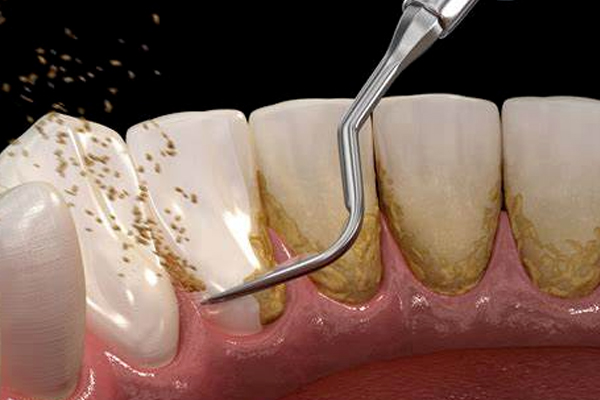

Scaling and polishing clean plaque and tartar buildup, refreshing your smile. This preventive care maintains gum health and prevents cavities, leaving teeth smooth and shiny. Regular cleanings are essential for a healthy, bright smile.